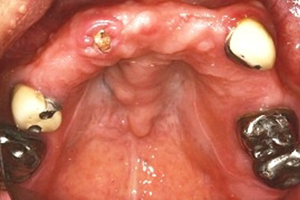

1. 多顆缺牙、牙周病、多顆蛀牙。

治療前-多顆缺牙及牙周病、蛀牙